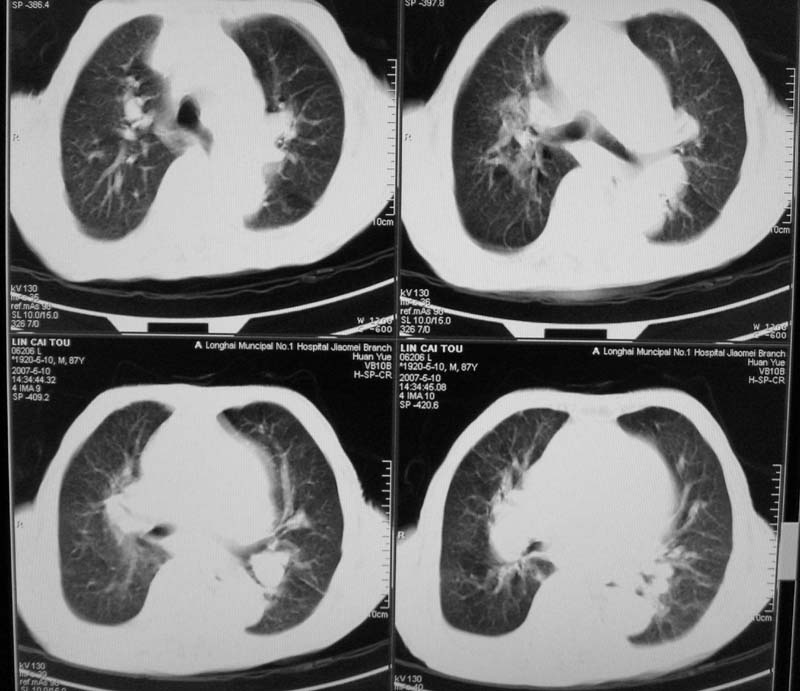

以下是引用小初学者在2007-5-12 16:26:00的发言:[br]1、心衰肺水肿两侧胸腔积液2、心包积液3、心瓣膜钙化